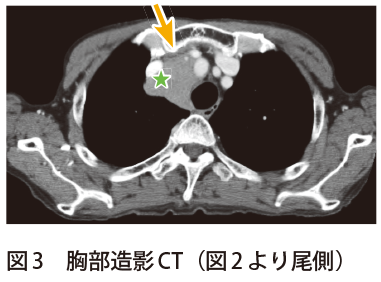

鎖骨下静脈〜左上肢中枢にかけての狭窄疑いとして,ct検査がオーダされ,画像診断科医師の要望により,(1) 単純,(2) 動脈相,(3) 静脈相で撮影を行った。 所 見左鎖骨下静脈は左第1肋骨と接しており,同部位で50%程度の狭窄を認める。に十分なct 値が得られ、pvpa の平均ct 値 差は分離可能なct 値差が得られている結果 となった。 fig1 pa とpv、pvpa のct 値 考察・結語 再考した1 相撮影において、肺動静脈ともにvr 作成に十分なct 値を保ちつつ、分離可能なct 値差左上腕:27 cm,左前腕:265 cmと右上肢の腫脹と皮下 静脈の怒張を認めた。 術前胸部造影CT 像(Fig 1A,B):冠状断像では右腕頭 静脈から分岐した右鎖骨下静脈が起始部から血栓閉塞し ているのが確認され,水平断像では右上腕の皮下静脈の 怒張を認めた。

左鎖骨下静脈およびその中枢静脈の狭窄の有無および, 外頸静脈へのバイパス作成による, 静脈系の減圧の可能性を確認するため, 静脈造影検査, および造影CT検査を行った鎖骨下静脈には狭窄, 血栓の所見はなく, さらに鎖骨下静脈と内頸静脈との合流部鎖骨下静脈(SV)の局所解剖(図2)7) 腋窩静脈(axillary vein,AV)は上腕静脈に続いて腋窩 部より起始し,肋骨前方で大胸筋後方に腋窩動脈と並 走する。腋窩三角に存在するこの区間では,皮下から 静脈に至る経路は深く,大胸筋と小胸筋により成る2 (211 中心静脈栄養の選択ルートはいくつかありますが、 内頸静脈や、鎖骨下静脈、下大総腸骨静脈などのルートは右側からが多いですよね。 そのことに疑問を投げかけてきた人がいまして、ちょうどいい機会なので調べてみました。 左からさすと胸管損傷をおこすからというおおざっぱな理由